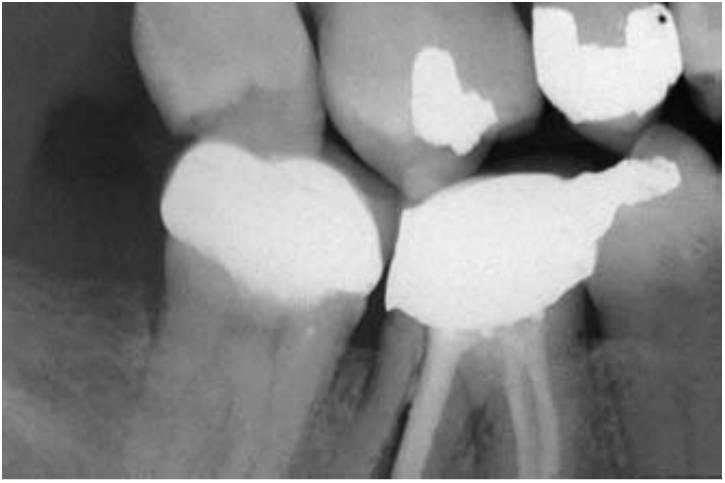

Las regiones posteriores de la boca suelen requerir la sustitución de un solo diente21'23 (fig. 1-5). Los primeros molares son el primer diente permanente en erupcionar en la boca y, desafortunadamente, suelen ser la primera pieza que se pierde por caries dentaria, fracaso de la terapia endodóncica o fractura (normalmente posterior a una endodoncia). Son dientes importantes para el mantenimiento de la forma de la arcada y de los esquemas oclusivos correctos. Adicionalmente, el paciente adulto suele llevar una o más coronas, como consecuencia de reparaciones importantes previas requeridas para reparar la integridad del diente. Los datos sobre la longevidad de las coronas han aportado resultados muy dispares.

Se ha observado que la vida media en el momento de la rotura es de 10 años. Otros datos revelan un rango de entre un 3% de fracaso a los 23 años hasta un fracaso del 20 % a los 3 años. La causa primaria del fracaso de la corona es una caries seguida de una terapia de endodoncia. El diente corre el riesgo de la extracción como resultado de estas complicaciones, que son las causas principales de la pérdida individual de un diente posterior en el adulto (fig. 1-6). Se ha evaluado que una corona de 245 dólares de valor en un paciente de 22 años supondrá un coste a lo largo de la vida del paciente de 12.000 dólares en repararlo/reemplazarlo.

Las consecuencias desfavorables del fracaso de una PPF incluyen la necesidad de reemplazar una prótesis que ha fracasado y la pérdida de un pilar, y la necesidad de pónticos adicionales y pilares dentales en el puente de sustitución. Se pueden perder los pilares dentales de una PPF hasta en un 30 % de los casos en un plazo de 14 años. Se pierden aproxi madamente entre el 8 y el 12% de los pilares dentales que sujetan una PPF en el plazo de los primeros 10 años. El mo tivo más común para la pérdida individual de un diente es el fracaso endodóncico o la fractura del diente (normalmente posterior a un tratamiento endodóncico). Por el hecho de que los pilares dentales requieren una endodoncia, y de que la terapia del canal radicular tenga éxito en el 90% de los casos en el plazo marcado de 8 años, los pilares dentales están más sujetos a sufrir caries cuando se encuentran inmovilizados mediante un póntico intermedio. Las coronas individuales tienen una media de incidencia de caries inferior al 2%; sin embargo, el riesgo de caries en los pilares dentales es del 20%, principalmente porque el área del póntico actúa como reservorio de placa. Una lesión de caries en un margen de la corona puede causar un fallo estructural, incluso siendo posible el tratamiento endodóncico (fig. 1-7).